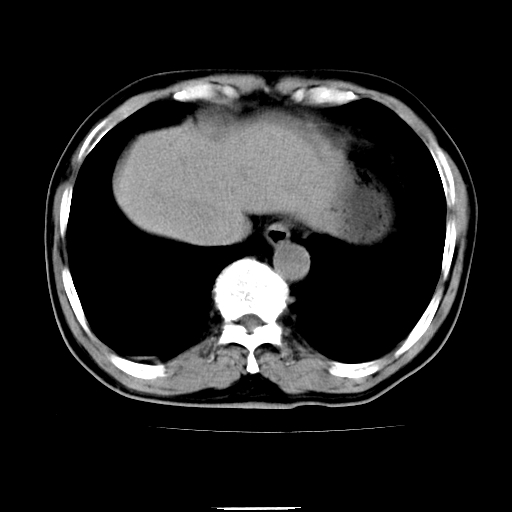

以下是引用chenqiong在2010-3-25 20:56:00的发言:[br]1、胆囊炎,胆囊息肉[br]2、肝内胆管及胆总管扩张,胆总管下端结石[br]3、十二指肠乳头旁憩室

以下是引用zxl51642在2010-3-26 10:47:00的发言:[br]胆囊炎,胆囊息肉,胆总管扩张,但未看到明显肿块,肝内胆管扩张不像恶性,炎性狭窄或阴性结石可能吧,建议mrcp,右肾小囊肿